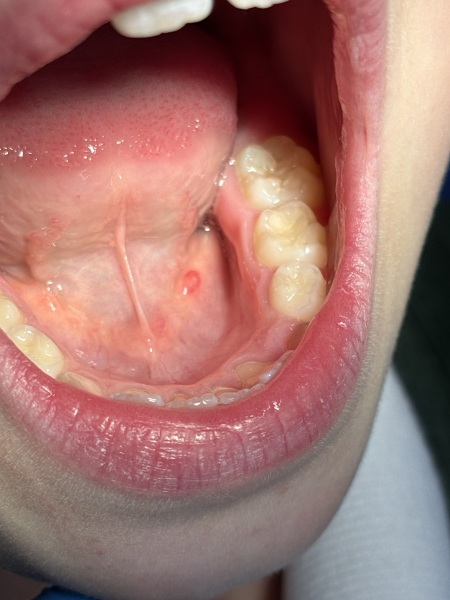

Just visited the dentist for our 6 monthly check up’s & the dentist pointed out my DD has this little pink lump under her tongue. We didn’t know this was there & this doesn’t bother her at all & she said it’s not painful. She wants her back in two weeks to check it.

Does anyone know what this could be? (Picture attached)

It doesn’t look like an ulcer I don’t think & the dentist said it could be a saliva stone - although said she’s quite young to get that.